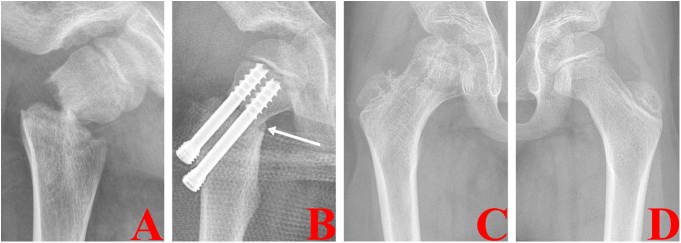

Figure 4.

Radiographs of different types of PFNFs according to the new classification system reported by Wang et al. (45), including type I without translation, type II with anterior translation, type III with posterior translation, type IV with a medial-posterior comminution (white arrow) and type V with the subtrochanteric femoral fracture.